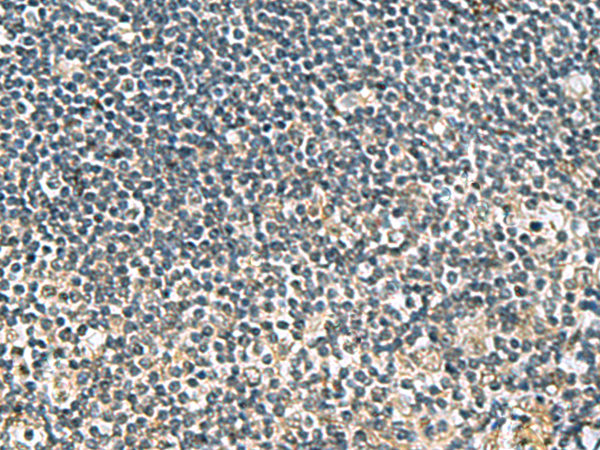

IHC positive control: |

Human tonsil and Human breast cancer |

IHC Recommend dilution: |

25-50 |